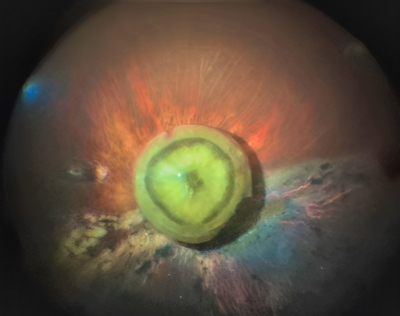

Bilateral Boston Keratoprosthesis for treatment of a variant of keratitis–ichthyosis–deafness syndrome